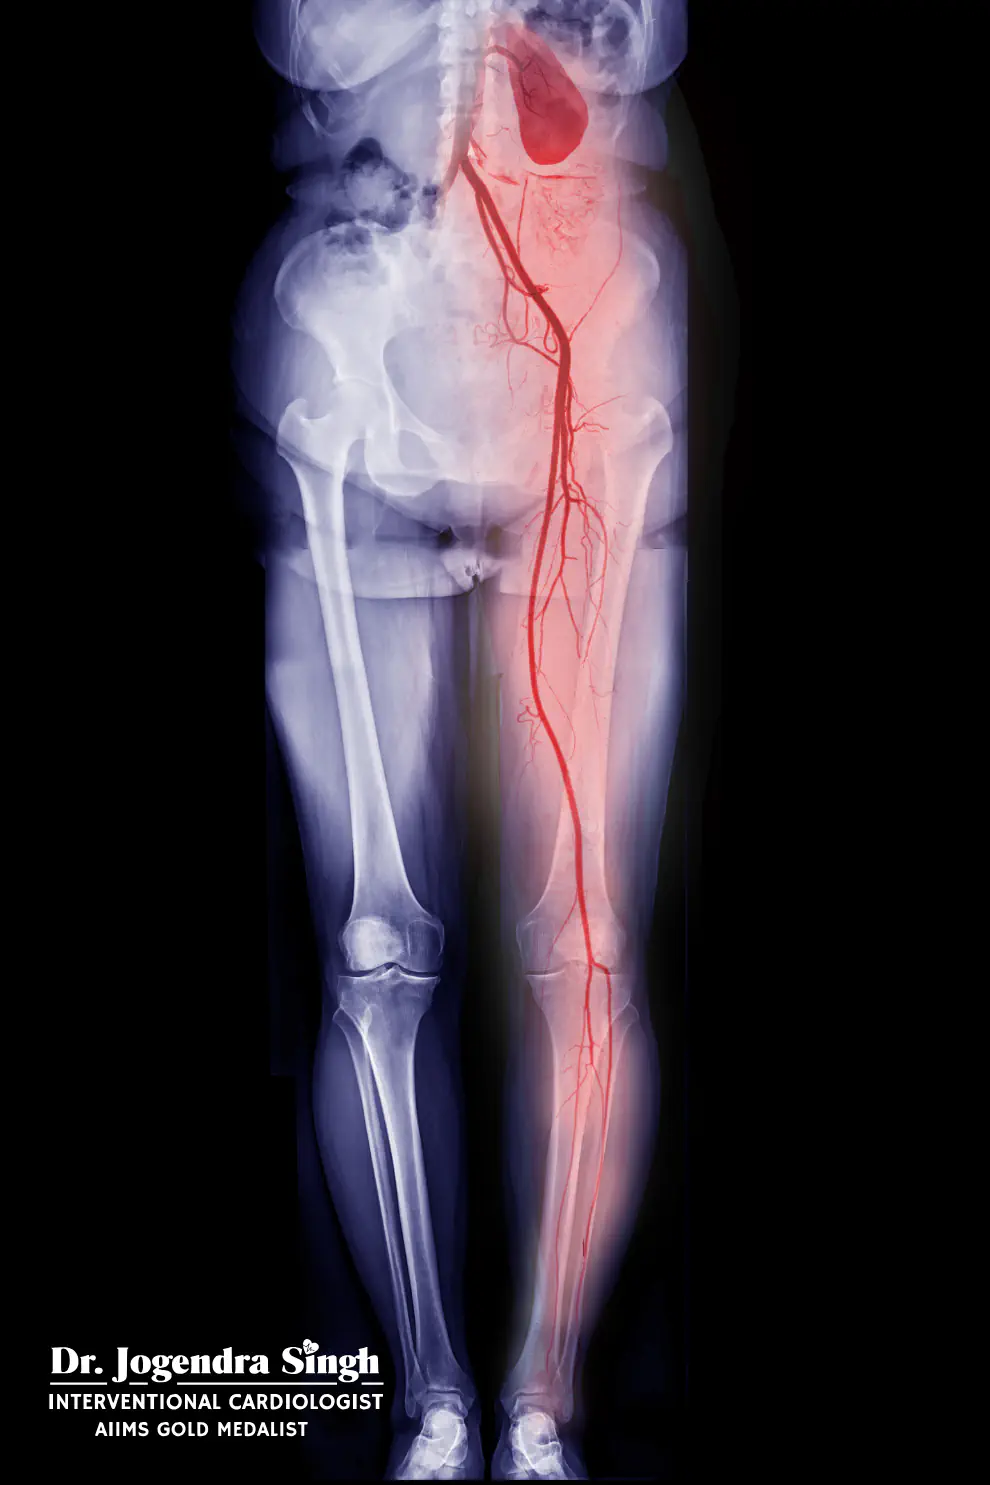

PERIPHERAL & NON-CORONARY INTERVENTIONS

Peripheral Angioplasty

Treats blockages in arteries of:

- Legs

- Arms

- Abdomen